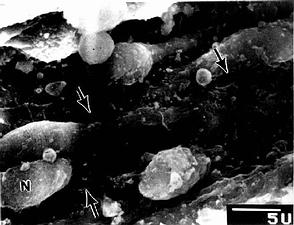

图9-22 大鼠脾血窦扫描电镜像

N内皮细胞核,↑内皮质间隙

脾血窦(splenic sinus):是一种静脉性血窦,宽约12~40μm,形态不规则,相互连接成网。窦壁由一层长杆状的内皮细胞平行排列而构成。内皮细胞之间常见许多0.2~0.5μm宽的间隙,脾索内的血细胞可经此穿越进入血窦(图9-21,9-22)。内皮外有不完整的基膜及环行网状纤维围绕,故血窦壁如同一种多孔隙的栏栅状结构。在血窦的横切面上,可见杆状内皮细胞沿血窦壁呈点状排列,较粗大的内皮细胞断面中可见有细胞核,并突入管腔(图9-19)。血窦外侧有较多的巨噬细胞,其突起可通过内皮间隙伸向窦腔。